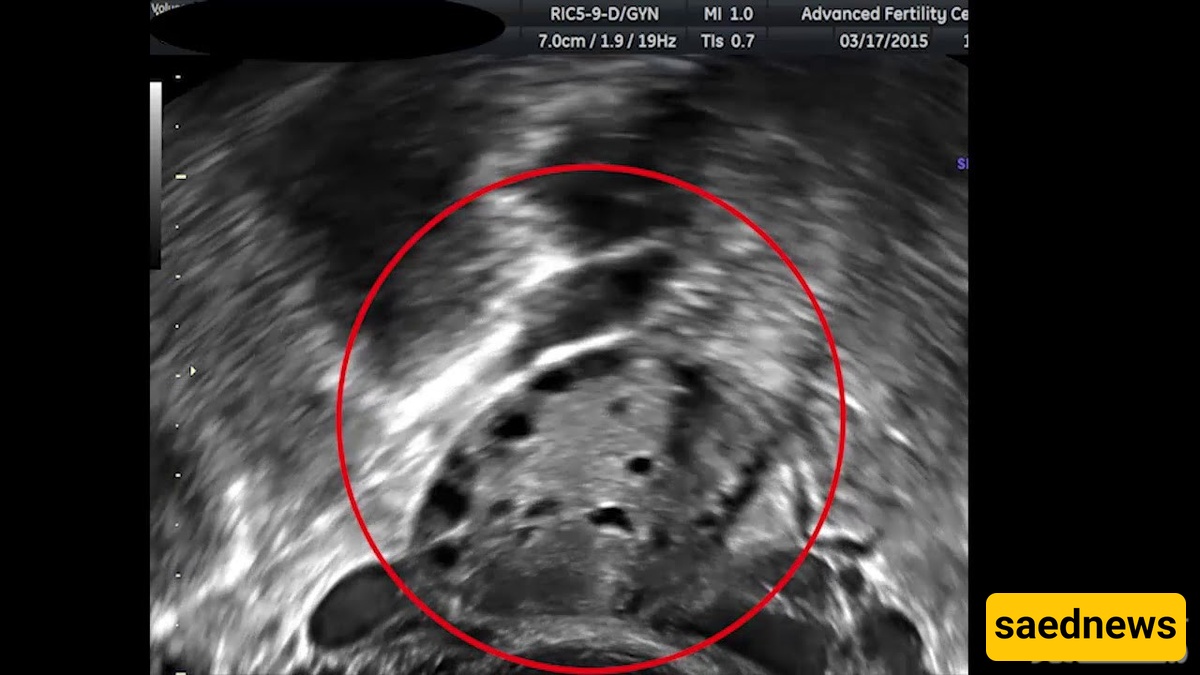

Adorable Ultrasound Image of a Pregnant Monkey

SAEDNEWS: Ultrasound Reveals the Fetus of a Pregnant Monkey